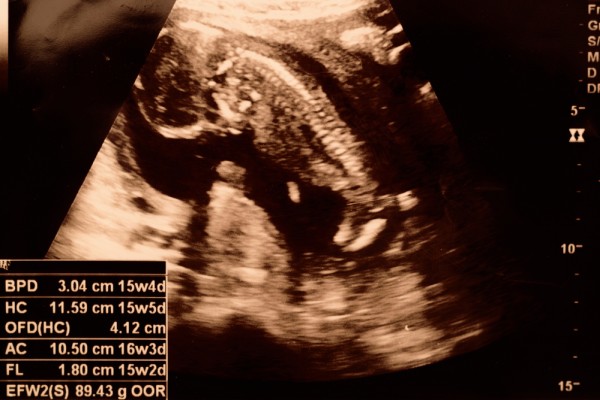

УЗИ

Ультразвуковое исследование на пятнадцатой неделе беременности проводится по желанию женщины или при наличии медицинских показаний. К таким показаниям относятся необходимость выявления замершей беременности или подтверждение отслойки плаценты.